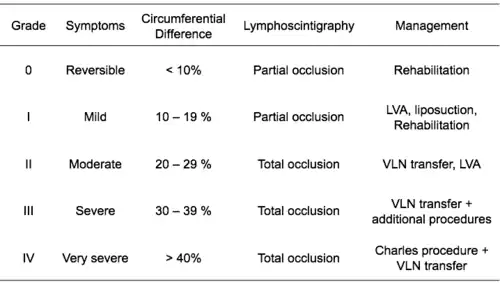

The International Society of Lymphology (ISL) Staging System is based solely on subjective symptoms, making it prone to substantial observer bias. Imaging modalities have been suggested as useful adjuncts to the ISL staging to clarify the diagnosis, such as Cheng's Lymphedema Grading tool, which assesses the severity of extremity lymphedema based on objective limb measurements and provides appropriate options for management.[39][40][41]

Lymphedema can also be categorized by its severity (usually compared to a healthy extremity):[46]

- Grade 1 (mild edema): Involves the distal parts such as a forearm and hand or a lower leg and foot. The difference in circumference is less than 4 cm (1.6 in) and no other tissue changes are present.

- Grade 2 (moderate edema): Involves an entire limb or corresponding quadrant of the trunk. Difference in circumference is 4–6 cm (1.6–2.4 in). Tissue changes, such as pitting, are apparent. The patient may experience erysipelas.

- Grade 3a (severe edema): Lymphedema is present in one limb and its associated trunk quadrant. Circumferential difference is greater than 6 cm (2.4 in). Significant skin alterations, such as cornification, keratosis, cysts or fistulae, are present. Additionally, the patient may experience repeated attacks of erysipelas.

- Grade 3b (massive edema): The same symptoms as grade 3a, except that two or more extremities are affected.

- Grade 4 (gigantic edema): In this stage of lymphedema, the affected extremities are huge, due to almost complete blockage of the lymph channels.